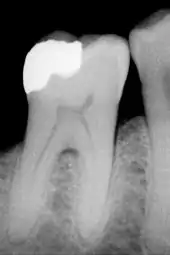

- En haut, l'émail composé principalement de la couche prismatique, et dans sa partie supérieure la couche finale sans bâtonnets. En bas, la dentine.